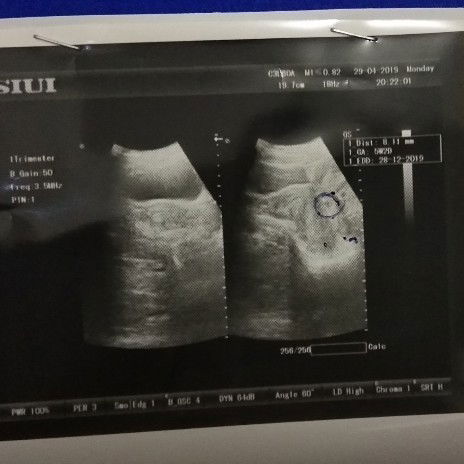

Ini hasil usg pertama kali cek ke dokter utk mastiin kalo aku beneran hamil (29 april 2019). Kata dokter iya aku lagi hamil udah masuk 6w, tapi waktu di usg dokter liat posisi calon janinnya gak seperti posisi pada umumnya. Dokter bilang kemungkinannya masih 50-50, 50% hamil atau 50% cuma hamil kosong. So, aku down dan takut banget... terus dokter nyaranin buat istirahat total, gaboleh makan ini itu, naik motor dll. Aku juga dikasih resep penguat janin & vitaminnya, dan disuruh balik lagi 4w kemudian utk usg kepastiannya...